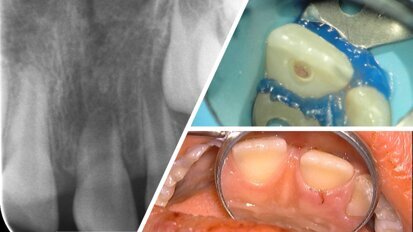

Prof. dr. Marcio Vivan Cardoso: “Een schoon oppervlak is de eerste voorwaarde”

De verschuiving naar partiële restauraties, die minder invasief zijn dan volledige kronen, is mogelijk geworden door de vooruitgang in tandheelkundige ...